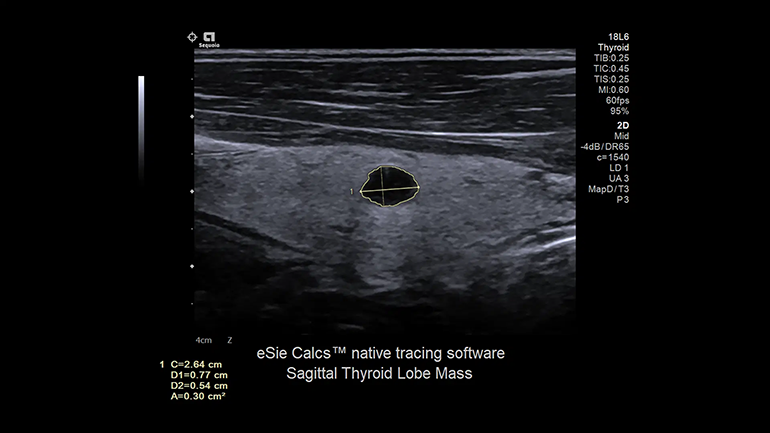

eSieCalcs​​

Встроенное программное обеспечение eSieCalcs выполняет быстрые автоматизированные линейные измерения трассировки, включая измерения расстояния, площади и окружности.